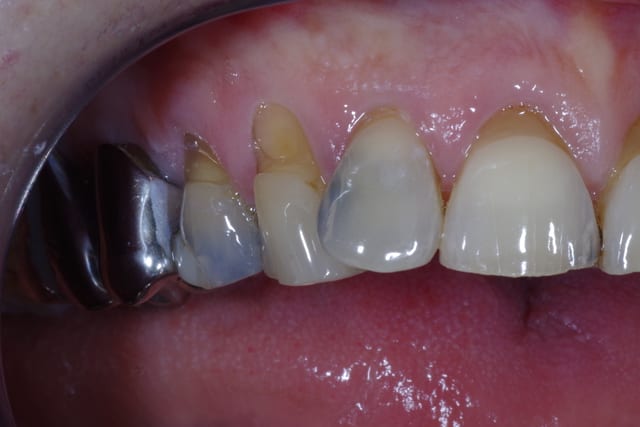

Je souhaiterais savoir comment vous gérer ces cas de mylolyses/érosions importantes sur les antérieures.

Pour le cas iconographié, je pensais à des facettes (histoire de donner une seconde jeunesse au sourire), mais je me demande comment réaliser mes préparations, s'il faut combler au compo pour éviter de surtailler autour, etc.

Avant d'envisager la moindre facette, il va falloir je pense revoir l'occlusion de ta patiente: courbe de Spee foirée à gauche, parafonction 21,22, vestibulo-version 12 suite DDM inf.

Après pour la partie technique pure au niveau antérieur, tout dépend de l'état d'usure palatine, et de lq stabilisation du bruxisme/parafonction, (comme demandé plus haut par GP) une photo occlusale peut nous guider pour connaître la meilleur thérapeutique à adopter, et l'éventail est large: du simple composite à la couronne périphérique en passant par la facette bilaminaire (au fait Gp se serait sympa de partager ce genre de cas avec les Nonoliens ;-)).

Ma question est purement technique. En palatin on ne note pas d'usure. Comment gérer la profondeur à rattraper, sur 23 par exemple, et comme tu l'indiques, Cingulum, quid de la qualité du collage sur ce type de dentine sclérosée? Avez-vous des trucs et/où astuces ?